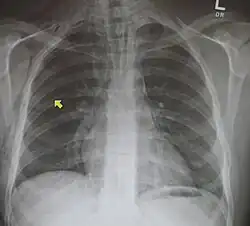

Mediastinalemphysem und rechtsseitiger Pneumothorax nach Rippenfraktur.